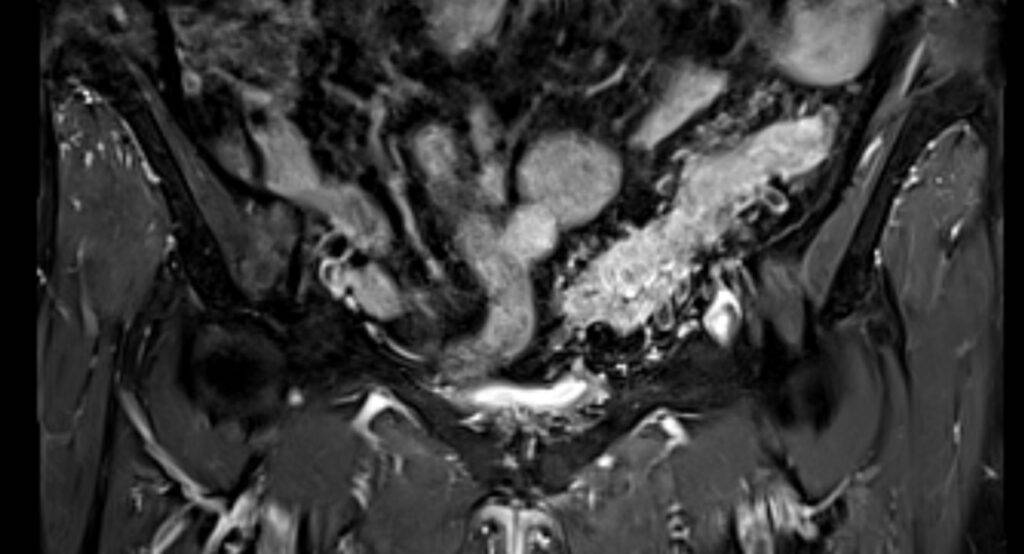

Die Magnetresonanztomographie des Abdomens, auch als MRT Abdomen bezeichnet, ist ein bildgebendes Verfahren, das magnetische Felder und Radiowellen verwendet, um detaillierte Bilder der inneren Strukturen des Bauchraums zu erzeugen. Der Bereich des Abdomen umfasst Organe wie die Leber, Milz, Bauchspeicheldrüse, Nieren, Magen, Darm.

Eine MRT Abdomen liefert besonders präzise Bilder des Bauchraums, da dieses Verfahren insbesondere weiche Gewebsstrukturen darstellen kann. Eine Magnetresonanztomographie (MRT oder auch Kernspintomographie genannt) ist ein Bildgebungsverfahren, welches die Darstellung des Körpers in mehreren Schichten und auf mehreren Ebenen ermöglicht.

Was kann man auf einer MRT des Abdomens sehen?

Auf einer MRT-Aufnahme sind insbesondere die Organe im Bauchraum sichtbar, da Weichteile in einer MRT sehr gut abgebildet werden können.

- Leber, Gallengängen, Bauchspeicheldrüse, Nieren und Nebennieren mit Harnleiter, Milz, Becken

Durch die detailreichen Abbildungen können Veränderungen der Organe festgestellt werden, die auf bestimmte Krankheiten schließen lassen – so können beispielsweise Entzündungen oder Gewebsveränderungen im Bauchraum festgestellt werden.

Es kann zwischen gut- und bösartigen Tumoren unterschieden werden. Dies ermöglicht eine genaue Diagnose, woraufhin ein schnelles und geeignetes Therapieverfahren angesetzt werden kann.